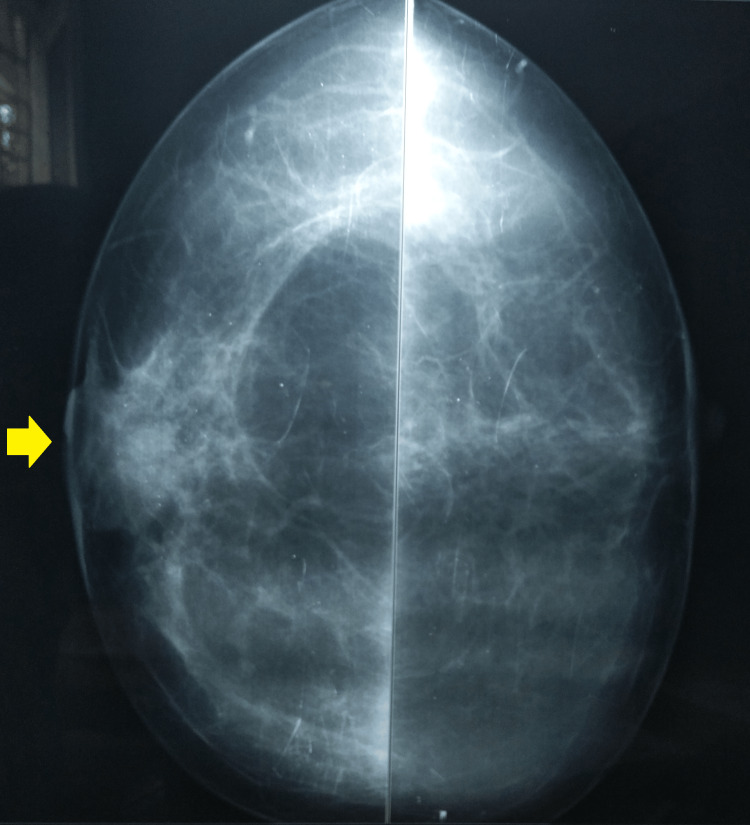

A breast mammography was suggestive of a 27 x 21 mm well-defined opacity in the retroareolar region of the right breast (Figures 3, 4).

Figure 3. Mammogram bilateral CC-view showing well-defined opacity and retracted right nipple.

CC: craniocaudal

Figure 4. A breast mammography (MLO-view) showing opacity in the retroareolar region of the right breast .

MLO: mediolateral oblique